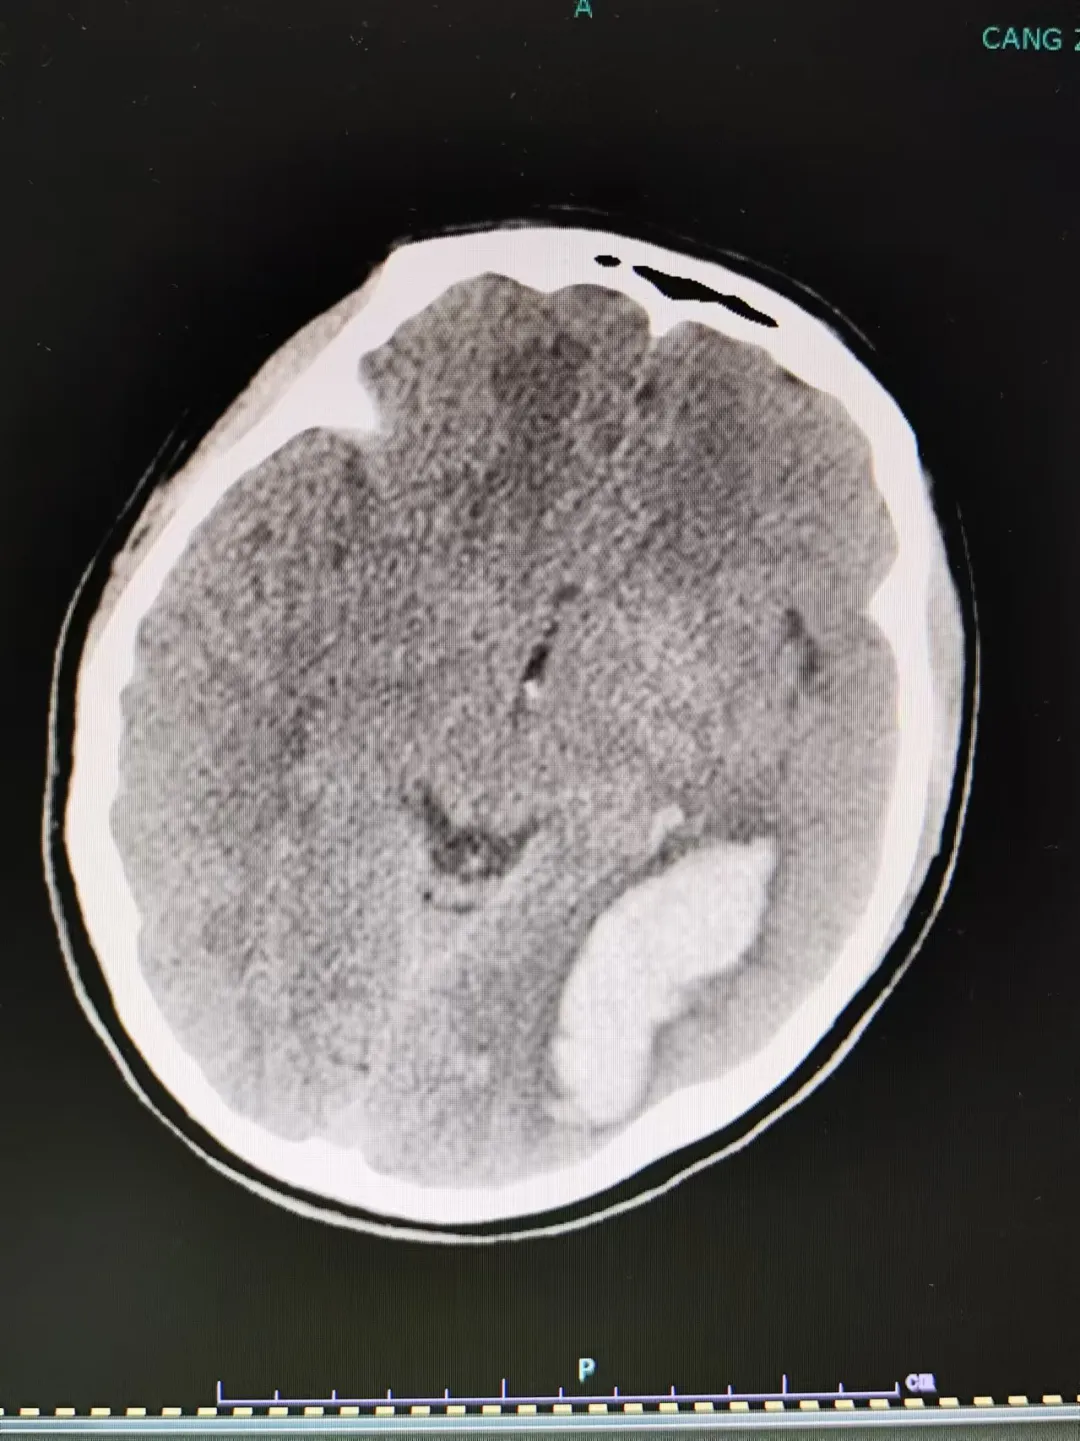

“叮鈴鈴,叮鈴鈴......”。凌晨一點,滄州市中心醫(yī)院神經(jīng)血管介入二科姜紅升醫(yī)生睡夢中被一陣急促的電話鈴聲吵醒,電話是某地縣醫(yī)院醫(yī)生打來的:一位高考完畢的18歲姑娘于夜間突然出現(xiàn)劇烈頭痛,伴惡心、嘔吐,隨后意識不清。這位患者被家屬送至當?shù)蒯t(yī)院,急查頭顱CT(圖一)示:左側(cè)顳枕葉腦出血破入腦室系統(tǒng),蛛網(wǎng)膜下腔出血。當?shù)蒯t(yī)院醫(yī)生隨即電話聯(lián)系姜紅升醫(yī)生并簡要說明了患者的基本情況。姜醫(yī)生了解相關情況后,依據(jù)患者為青年女性,既往體健,查體情況以及影像學結果提示,考慮腦動靜脈畸形破裂出血可能性大。姜紅升醫(yī)生、當?shù)蒯t(yī)院醫(yī)生同患者家屬緊急商議,最后家屬決定將患者轉(zhuǎn)至滄州市中心醫(yī)院腦科院區(qū)繼續(xù)治療?;颊咿D(zhuǎn)入滄州市中心醫(yī)院后完善查體:意識不清,精神差,反應遲鈍,刺痛可發(fā)音,雙側(cè)瞳孔正大等圓,對光反射遲鈍,頸項強直,刺痛四肢可動,巴氏征(-)。為預防腦疝形成,醫(yī)生們緊急對患者行“腦室外穿刺引流術”。 姜紅升醫(yī)生考慮,腦血管畸形出血情況不明下貿(mào)然手術可能會出現(xiàn)術中大出血、腦腫脹、畸形團位置不明確等嚴重后果,并且腦血管畸形存在著再次破裂出血、癲癇等可能性。遂向患者家屬交待行腦血管造影及視情況行介入治療的必要性?;颊呒覍俦硎局槔斫?,并同意造影及后續(xù)介入治療操作。姜紅升醫(yī)生遂于當日上午對患者行腦血管造影檢查。 患者造影結果提示:左側(cè)顳枕部動靜脈畸形,左側(cè)大腦后動脈顳后動脈分支主要供血,左側(cè)大腦中動脈少量供血,畸形團約2cm,通過橫竇引流。 了解造影結果后,姜紅升醫(yī)生與科室各位醫(yī)生對適合患者的治療方式進行討論:外科手術是當前治療腦血管畸形的主要方法,其優(yōu)勢在于根除病變部位,避免再次復發(fā);但手術前需要仔細研讀影像資料,了解畸形血管團生長的位置、大小、是否位于功能區(qū)、正確識別主要的供血動脈和引流靜脈等等,評估術中大出血、惡性腦腫脹、術后神經(jīng)系統(tǒng)功能缺損的風險,對手術方案的制訂和實施至關重要。介入治療創(chuàng)傷小,對于處理深部、功能區(qū)等手術無法切除的腦動靜脈畸形具有明顯優(yōu)勢;但介入治療相較于外科手術亦存在諸多不足:如不能達到治愈性栓塞,因改變畸形血管團的血流動力學,反而增加再次破裂出血的風險;栓塞材料的移位亦可能導致正常血管的閉塞,引發(fā)神經(jīng)功能障礙;以及介入治療后術后存在高復發(fā)率等等。本例患者畸形血管團位于非功能區(qū),其體積較小,合并顱內(nèi)出血,擬為患者行“介入栓塞+外科手術切除”治療策略:首先對腦血管畸形團供血動脈進行栓塞,降低畸形血管團血流量,從而大大降低后續(xù)外科手術切除過程中發(fā)生出血、腦腫脹的風險,提高外科手術的安全性,然后再對患者進行外科手術治療,達到根除病灶的效果。制訂出該患者治療策略后,姜紅升醫(yī)生對患者家屬充分交待病情以及手術方案,得到家屬的理解與同意。 團隊遂于介入導管手術臺上開始對患者畸形血管團進行介入栓塞,經(jīng)Marathons微導管向主要供血動脈及畸形血管團,分次注入Onyx膠。再次造影,提示畸形血管團殘余少量顯影,主要供血動脈消失,余血管未見異常。 栓塞術后待患者略恢復后,完善磁共振掃描等相關檢查,嚴密制訂手術計劃,于數(shù)天后行“腦血管畸形切除術”。顯微鏡下熒光造影,識別主要引流靜脈,確認后保護好引流靜脈,沿畸形血管團切除及清除顱內(nèi)出血,待完整切除動靜脈畸形團后,將引流靜脈電凝切斷。術后給予患者對癥治療,經(jīng)過積極治療,患者恢復良好,未遺留明顯后遺癥,順利出院。 在患者出院后,姜紅升醫(yī)生也收到了該患者被大學錄取的喜訊。出院后的患者即將迎來嶄新美好的大學生涯。 溫馨提示 年輕、既往無高血壓病史患者,如出現(xiàn)腦出血,務必考慮到腦血管畸形的可能性,盡量爭取機會完善相關檢查,確定患者腦出血的病因,并根據(jù)患者實際情況,嚴密制訂合理的治療策略。如貿(mào)然為患者行顱內(nèi)血腫清除術,可能會導致術中大出血,惡性腦腫脹等惡性事件,導致患者出現(xiàn)致死致殘的災難性后果。